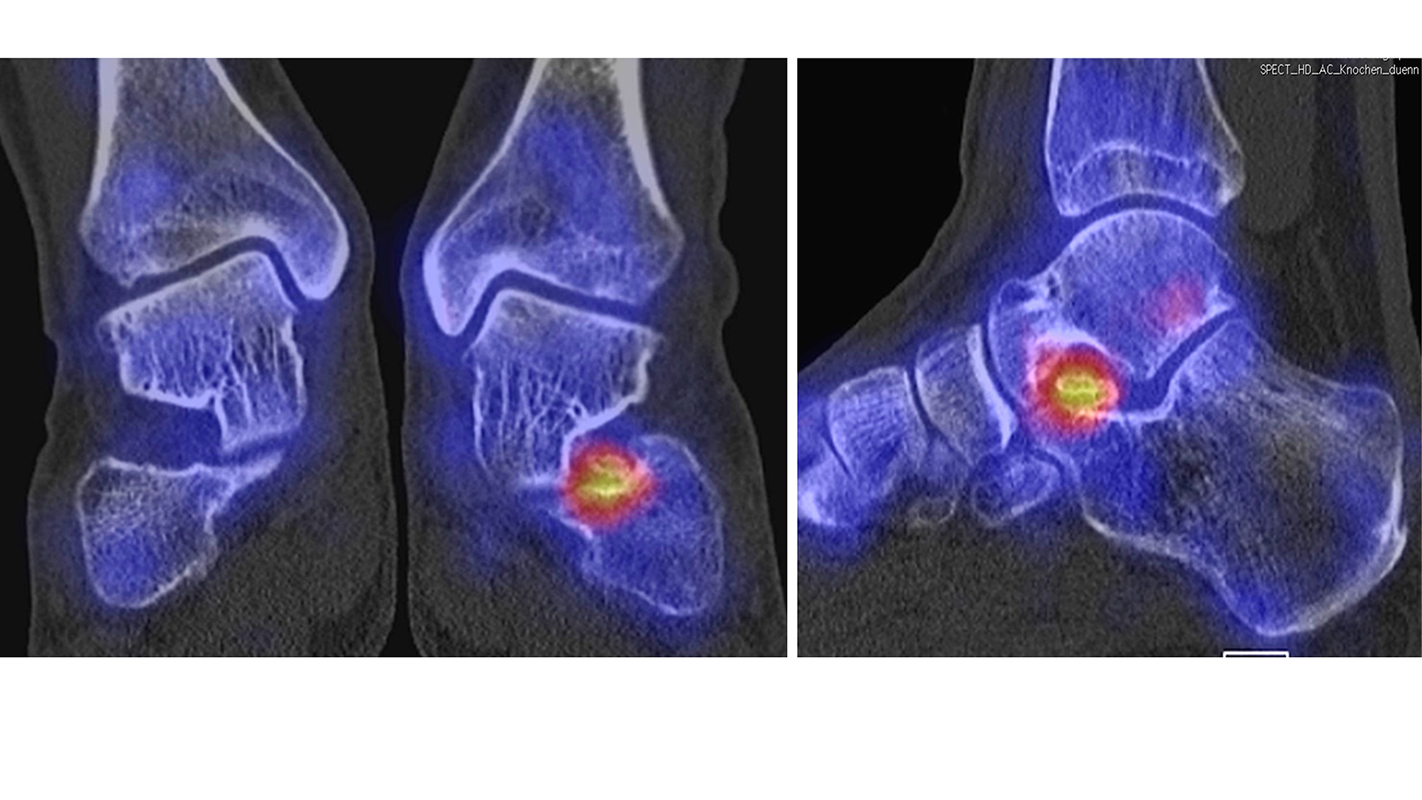

Die Abbildungen 4.2.a bis d zeigen den typischen Aspekt einer talacalcanearen Coalitio. Es besteht nur eine linksseitige, symptomatische Coalitio talocalcaneare (4.2.a und c); das 35 Tage zuvor angefertigte MRT zeigt keine auffälligen Signalveränderungen (4.2.b und d).

Coalitionen können auf Röntgenbildern wegen überlappender Strukturen häufig nicht sicher diagnostiziert werden, so dass MRT und/oder CT erforderlich sind, um eine Coalitio eindeutig nachzuweisen. Der Vorteil der SPECT/CT liegt darin, dass neben der submilimeter-genauen Darstellung der Anatomie, womit die charakterischten Röntgenzeichen einer Coalitio erkannt werden, auch die Stressreaktion bzw. die Scherkräfte, die auf die Syndesmose oder Synchondrose wirken, sichtbar gemacht werden können. Dabei hat die SPECT/CT eine deutlich höhere Treffsicherheit als die MRT zur exakten Lokalisation der Stressreaktion 44.